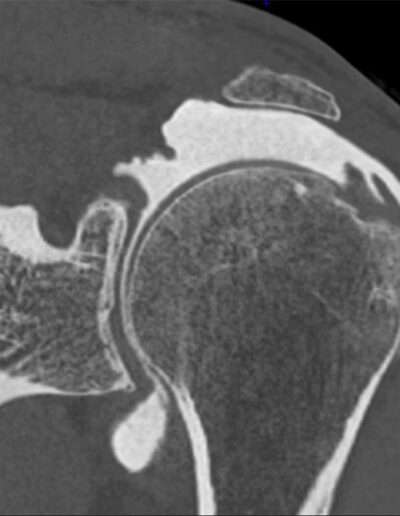

Shoulder Right

Patient 76 y/o, Male, right-handed

• 03/2021: Supraspinatus + Infraspinatus double-row repair (Dr. Laurent LAFOSSE)

• 06/2021: Revision SSP+ISP double-row repair (Dr. Laurent LAFOSSE)

• 12/2024: Pain and weakness in ER2